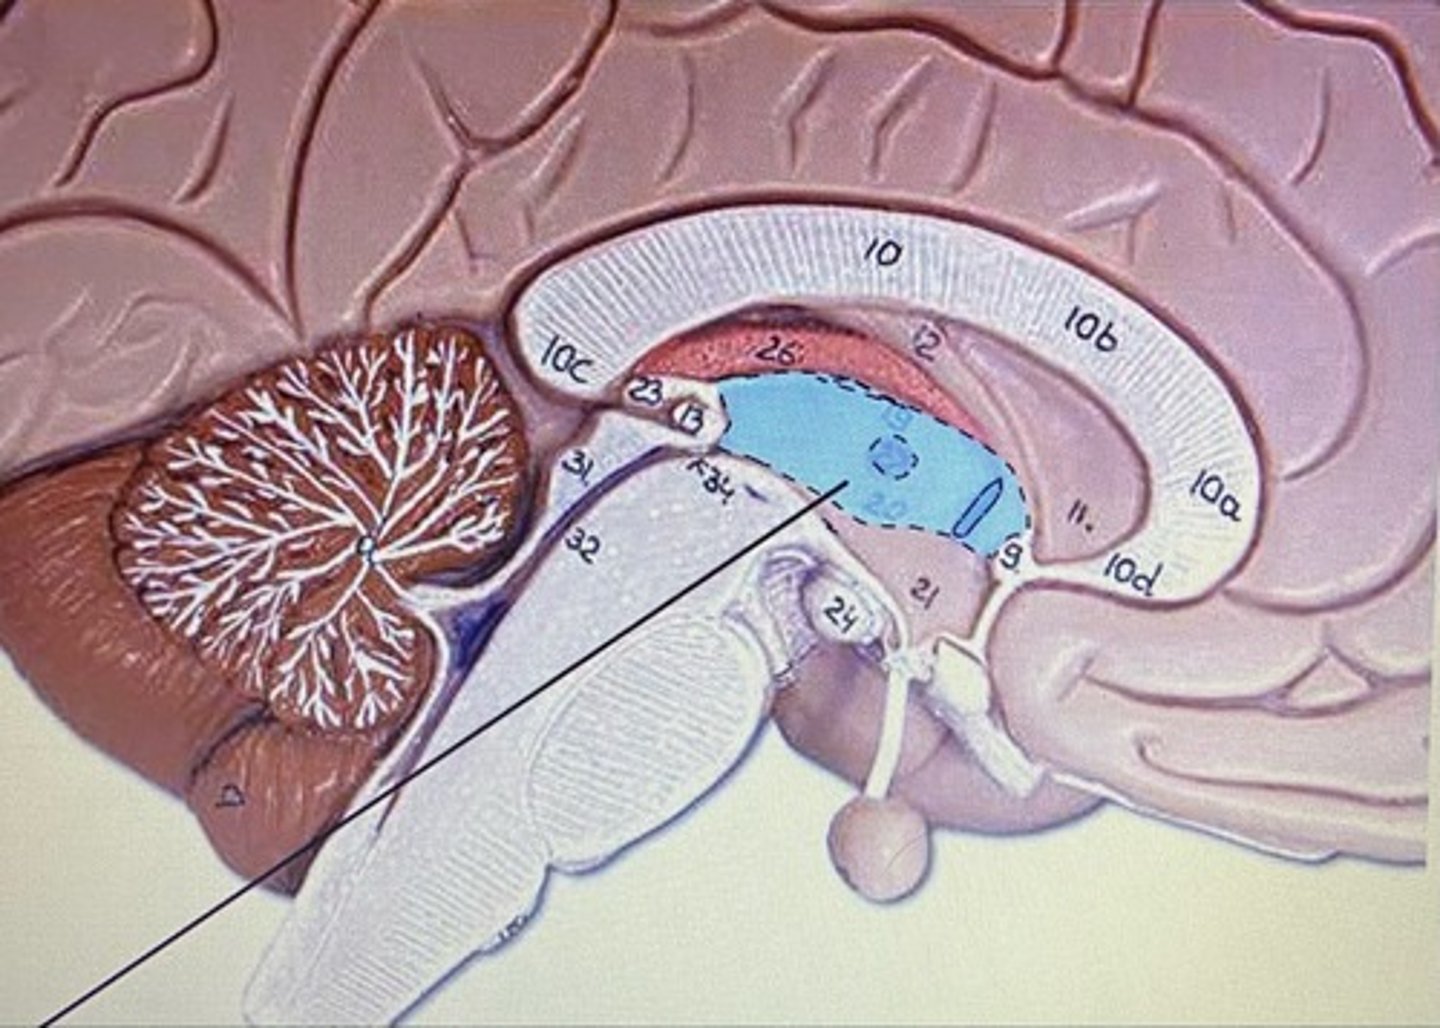

Cerebellum

Arbor Vitae

Medulla Oblongata

Pineal Body/Gland

Superior Colliculus

Inferior Colliculus

Third Ventricle

Fourth Ventricle

Cerebral Aqueduct

Cerebellum

-coordinates muscles movements, muscle memory

Transverse Fissure

-separates cerebrum & cerebellum

Inferior Colliculi

-auditory reflexes

Superior Colliculi

-visual reflexes

Pineal Body

-controls sleep/wake cycles

Pons

-bridge that links medulla oblongata to thalamus

Medulla Oblongata

-houses autonomic centers